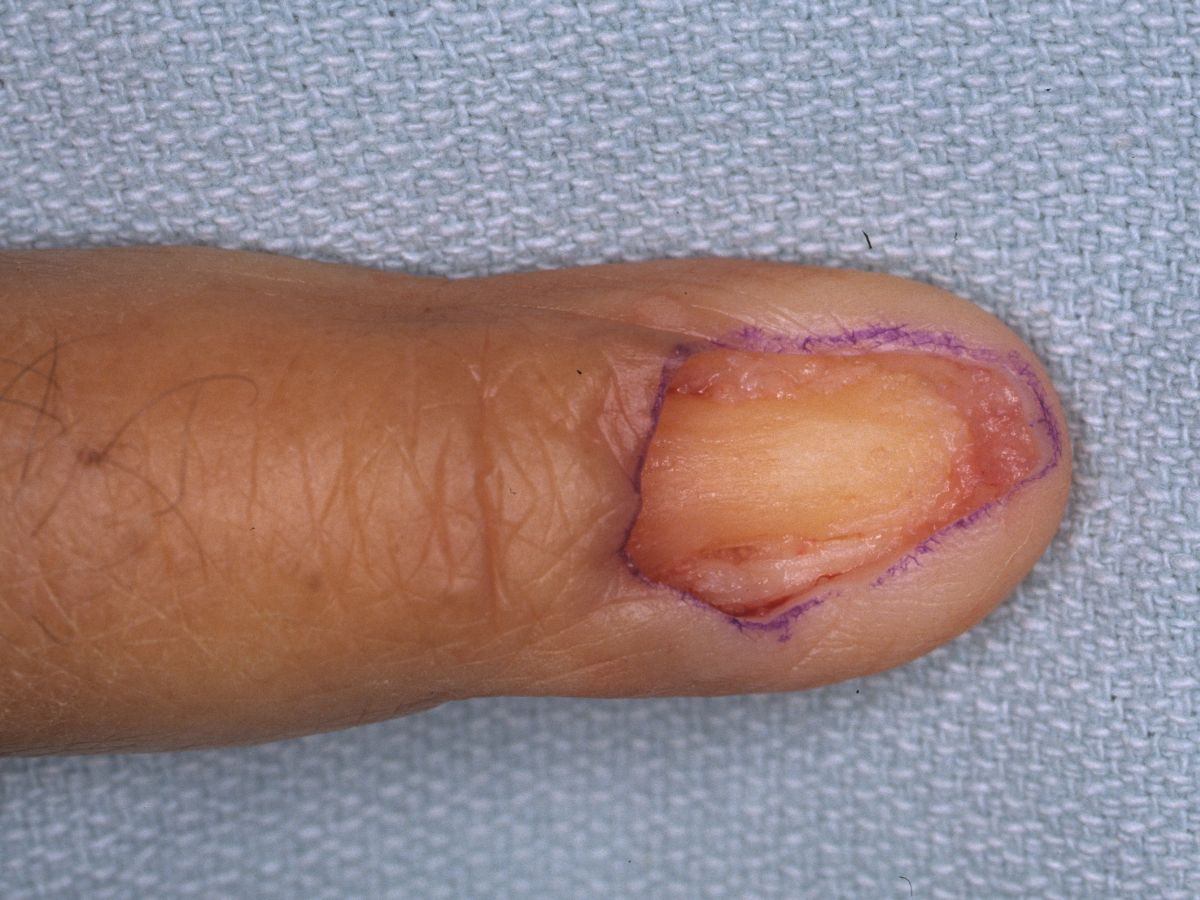

Defect following en bloc resection of entire nail complex.

Full thickness skin graft from proximal medial forearm. Everting horizontal mattress sutures maximize graft contact area.

Case 1.

Biopsy proved superficial squamous cell carcinoma of the nail bed.